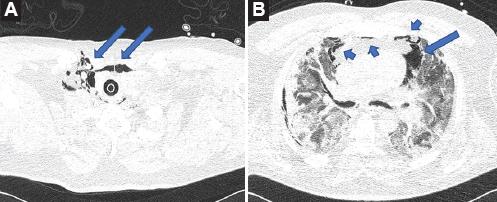

Figura 2 A: Tomografía axial computarizada realizada al ingreso; se aprecia neumomediastino y enfisema subcutáneo (flechas). B: Tomografía axial computarizada realizada al ingreso; se observan áreas de consolidación pulmonar bilateral y áreas de vidrio despulido bilaterales. Neumomedastino (flechas).

Del 28 de febrero al 30 de septiembre de 2020, 1300 pacientes ingresaron al Instituto Nacional de Enfermedades Respiratorias, Ciudad de México, con el diagnóstico de COVID-19, confirmado con PCR de exudado faríngeo o nasal. Seis pacientes masculinos con edades entre 27 y 82 años presentaron NM espontáneo y enfisema subcutáneo. Cuatro pacientes presentaron NM espontáneo y enfisema subcutáneo antes de su llegada al servicio de urgencias y dos, 24 horas después de haber sido intubados para apoyo mecánico ventilatorio. Un paciente llegó al Departamento de Urgencias con enfisema subcutáneo en cabeza, cuello, tórax y ambos brazos, así como NM diseminado (Figura 1); fue intubado a su ingreso debido a la severidad de la insuficiencia respiratoria. Cinco pacientes presentaron enfisema subcutáneo y NM leve. En las tomografías axiales computarizadas de todos los pacientes se observaron imágenes de vidrio despulido y áreas de consolidación en ambos campos pulmonares (Figuras 1, 2 y 3).